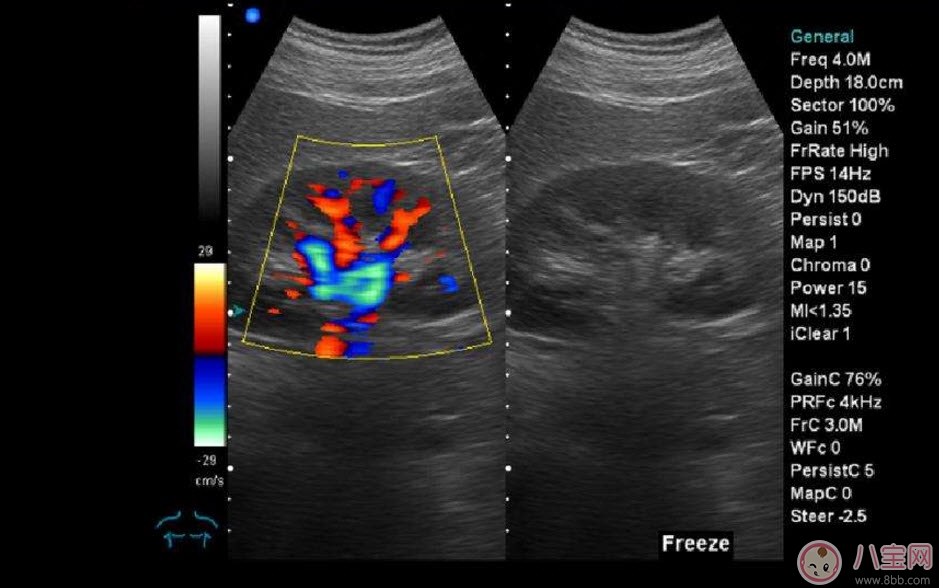

??B超也稱為二維超聲,分為黑白的和彩色的兩種。 彩超其實還是黑白的,彩超簡單的說就是高清晰度的黑白B超再加上彩色多普勒,既具有二維超聲結構圖像的優(yōu)點,又提供了血流動力學的豐富信息。彩超的分辨率會比一般黑白B超高一些,所以在需要做比較細致的檢查的時候,更多的醫(yī)生愿意通過彩超來檢查。例如,因為彩超能用彩色標注血流,所以當臍帶繞頸的時候就會看見寶寶的脖子上呈U形或者W形的血流,對是否臍帶繞頸也就一目了然了。目前用于產檢的超聲波一般都是二維的。

除了能觀察到通過B超觀察到的一切外,彩超能夠直觀成像,顯示更清晰,結果也更快速,可發(fā)現(xiàn)異常血流,為診斷胎兒先天性心臟缺陷提供了診斷依據(jù)。價格要比B超貴,大概在150元左右(會根據(jù)各地具體情況的不同而上下浮動)。二維彩超適用于整個孕期,特別是臨產前。二維彩超的圖像也并非就是彩色的,而是用彩色標注心臟、血流等指標,其實就是高清晰度的黑白B超再加上彩色多普勒。觀測到的圖像以紅藍兩色血流方向為主,面向探頭的呈現(xiàn)紅色,反之為藍色。這種技術能夠觀測到胎兒的血液流動情況,有利于及時發(fā)現(xiàn)胎兒的異常。比如,發(fā)現(xiàn)胎兒頸部有血流環(huán),則意味著發(fā)生了可導致窒息死亡的臍帶繞頸。